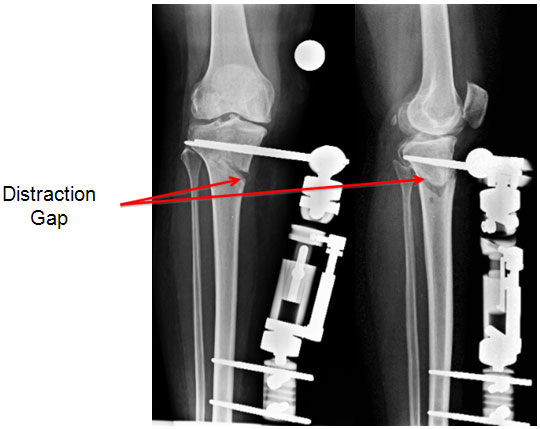

| 2 weeks post surgery |

| The gap at the osteotomy increases as distraction goes on, changing the angle with it. |